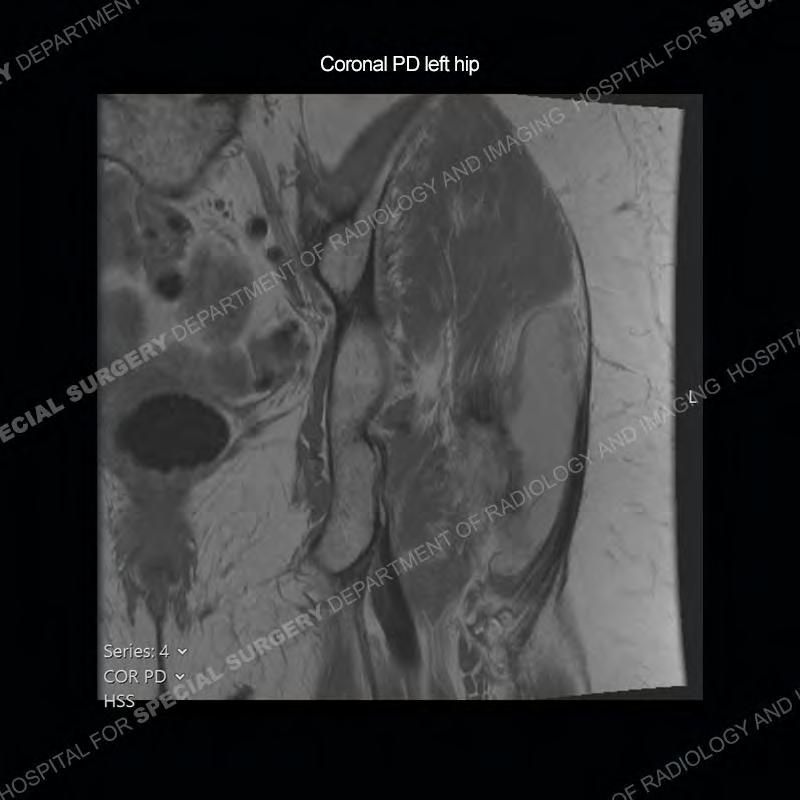

The radiograph is not particularly contributory in this case. The MRI demonstrates markedly abnormal architecture of the gluteus minimus and anterolateral band of the gluteus medius. Portions of the tendons are high signal, portions are highly attenuated, and portions are disrupted. A large, complex fluid collection is present in the adjacent soft tissue.

Diagnosis: Gluteal Tendinosis and Disruption with Complex Trochanteric Bursal Collection

Not as much of a diagnostic dilemma as many of the other cases shown but just a nice example of the pathology seen of the gluteal tendons and a cause of trochanteric pain. Although, frequently thought of in isolation, trochanteric bursitis or bursal thickening is much more commonly a reactive change to underlying pathology of the subjacent gluteal tendons. The gluteus medius is divided into a posterior band and an anterolateral band. Tendinosis and partial tearing very commonly will involve the gluteus minimus and especially the more posterior fibers and then propagate into the anterior lateral band of the gluteus medius. Involvement of the posterior band of the medius is much less common and engenders a marked degree of functional impairment.

The bursae about the greater trochanter can be a little bit confusing especially given the terminology. Trochanteric bursitis is implied to mean the subgluteus maximus bursa which is present deep to the maximus and just lateral/superficial to the trochanter. That is the bursa involved in this case. In this case the complexity of the bursa relates to the tendon tearing with inflammatory change and probably hemorrhage accounting for the complexity. Two other, less frequently involved bursa are also present. The subgluteus medius and subgluteus minimus bursa are found just deep to the named tendons. Although pathology does frequently follow the previously described pattern it is possible to have isolated pathology to either the medius or minimus.